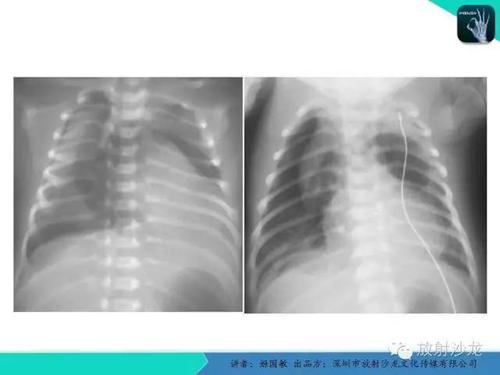

新生儿呼吸困难肺部x线诊断